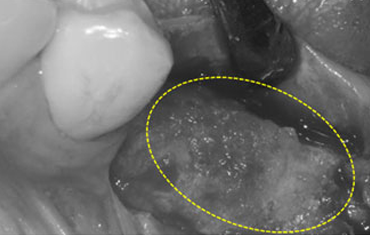

타 치과의 뼈 이식 후 골조직

램브란트치과 상인점 뼈이식 후 골조직